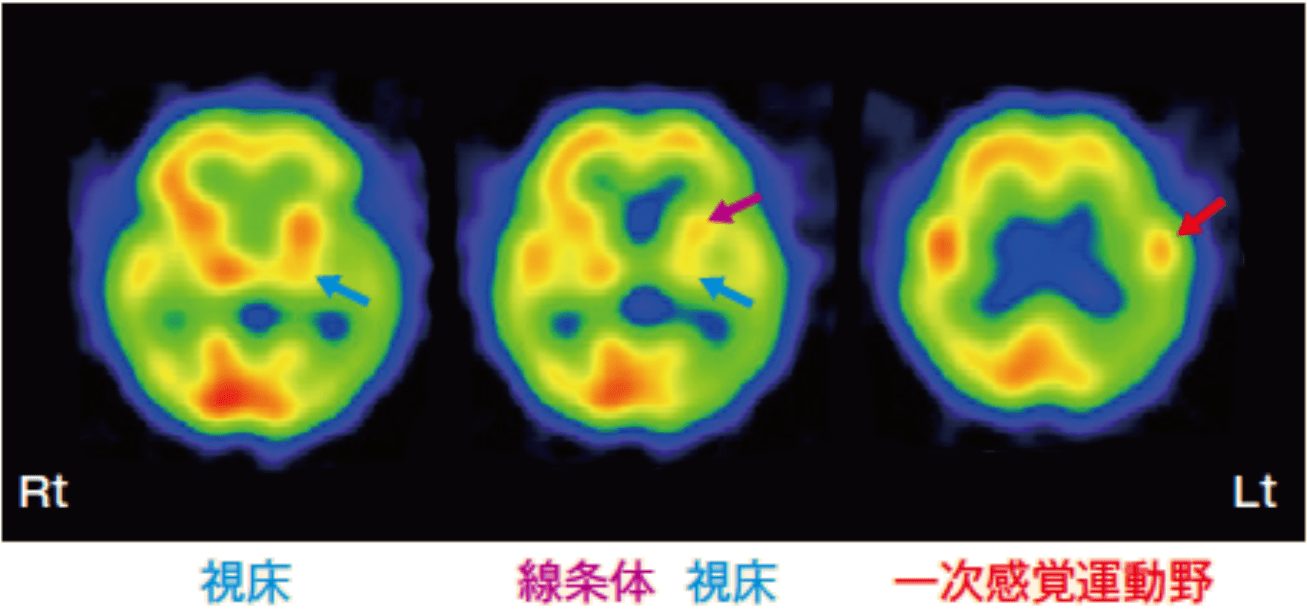

脳のSPECT 機能画像のよみ方・使い方 脳血流SPECT画像 認知症原因疾患ごとの血流分布と読影の注意点1の詳細情報

脳血流SPECT画像 認知症原因疾患ごとの血流分布と読影の注意点1。脳血流SPECT統計解析ソフトウェア (e-ZIS) が新しくなりました。SPECT検査 横浜市。脳のSPECTに関する機能画像の解説と使用法を詳述した専門書。RI検査(SPECT:スペクト検査)|放射線科|診療科のご案内。- タイトル: 脳のSPECT 機能画像のよみ方・使い方- ISBN: 9784524201716- 価格: 15000円ご覧いただきありがとうございます。ぜりー様、専用。